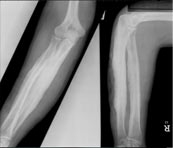

Koch's elbow